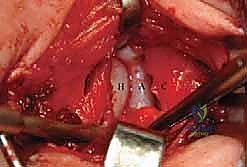

الخطوة 6: تنظيف التجويف الحقي (Clearing the Acetabulum)

الآن، يرى الجراح داخل المفصل. هنا تبرز الخبرة في إزالة العوائق الداخلية:

* يتم استئصال الرباط المدور (Ligamentum Teres) المتضخم الذي يشغل حيزاً كبيراً.

* يتم إزالة الأنسجة الليفية والدهنية المعروفة باسم البولفينار (Pulvinar).

* يتم شق الرباط الحقي المستعرض (Transverse Acetabular Ligament) إذا كان ضيقاً ويمنع دخول رأس الفخذ.

الخطوة 7: الرد الفعلي للمفصل (Reduction)

بعد تنظيف التجويف تماماً، يقوم الدكتور هطيف بتوجيه رأس عظم الفخذ بلطف شديد ليدخل ويستقر بعمق داخل التجويف الحقي. يجب أن يكون الرد مستقراً وسلساً دون الحاجة إلى قوة مفرطة. يتم فحص استقرار المفصل في وضعيات مختلفة للتأكد من عدم خروجه مرة أخرى.